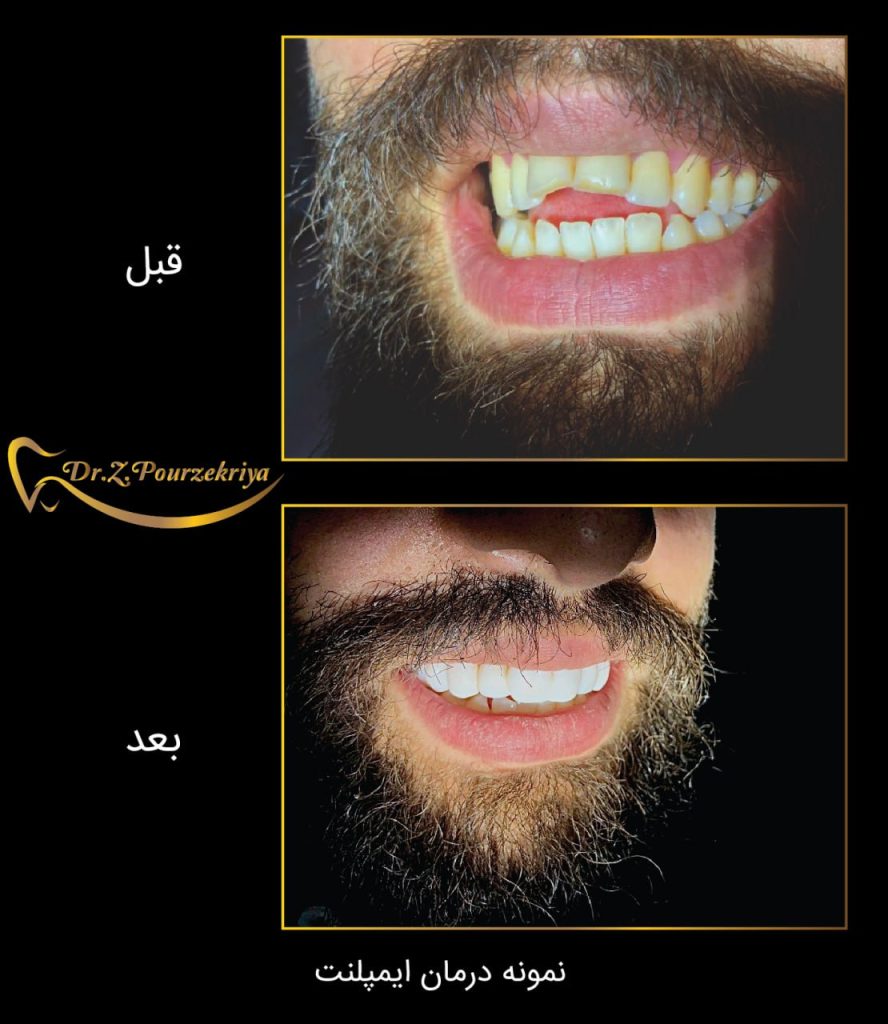

بازسازی دندان ها با روش برتر ایمپلنت

راهی برای زیبایی ، سلامتی

و لبخندی درخشان

بازسازی دندان ها با

روش برتر ایمپلنت راهی برای زیبایی

سلامتی و لبخندی درخشان

ایمپلنت دندان راه حل نهایی بی دندانی

ایمپلنت دندانی یک روش درمانی است که از طریق جایگزینی دندان طبیعی با دندان مصنوعی میباشد. این دندان ها از موادی مانند فلز تیتانیوم ساخته شدهاند و به استخوان فک یا لثه متصل میشوند.

- بازگردانی زیبایی و عملکرد با ایمپلنت دندان

- سلامتی و زیبایی با ایمپلنت

نمونه های درمان

دکتر زکیه پور ذکریا، جراح دندانپزشک و ایمپلنتولوژیست :

ورضایت مراجعین برایم بزرگترین تبلیغ محسوب میشود